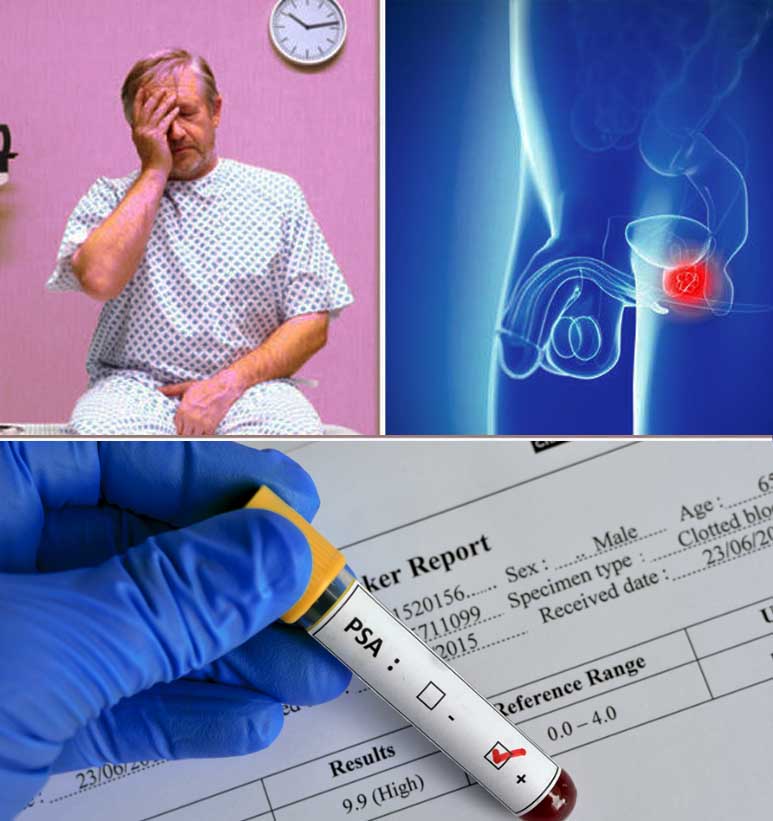

Should You Be Screened for Prostate Cancer?

Early Warning Signs of Prostate Cancer – Hello Doctor

What are the most common earliest symptoms of prostate cancer? – Quora

The Problem with PSA Screenings, Prostate Cancer and Risk

Symptoms of Prostate Cancer, Risk Factors and Causes – My Health Only

Prostate Cancer – Screening Saves Lives